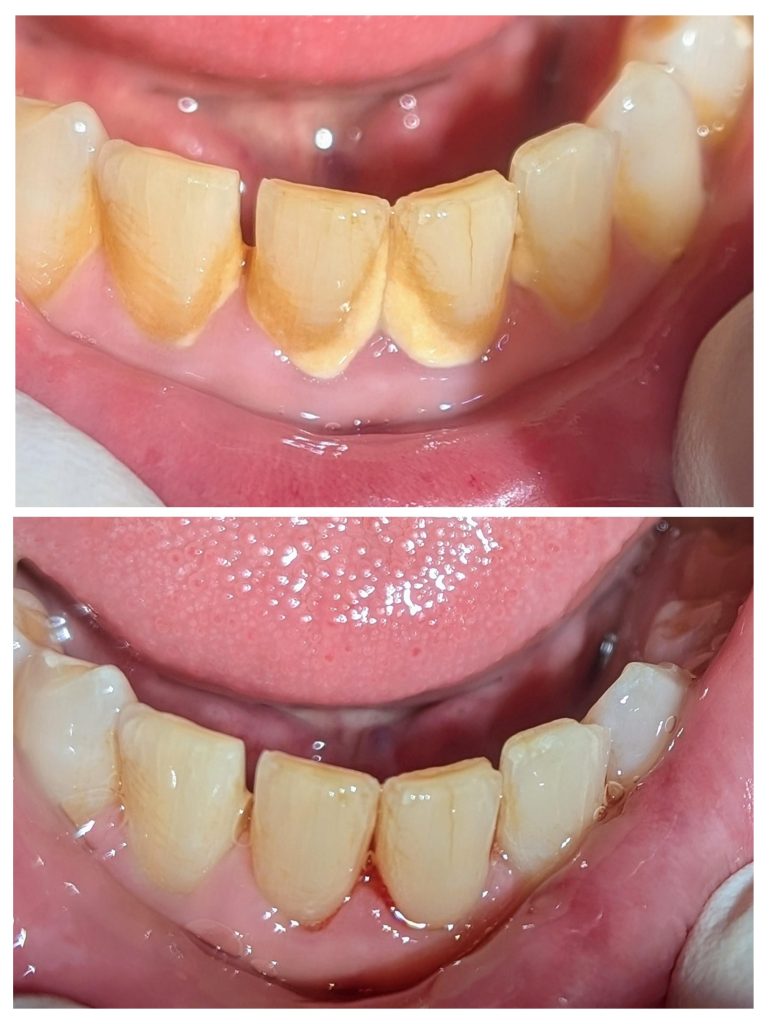

ANBIシドニーでは、ほとんどの治療にマイクロスコープを活用。

肉眼では見えない歯石や汚れをしっかり捉え、

歯茎に優しい

痛みが極めて少ない

効果が長持ち

という、ワンランク上のクリーニングを可能にしています。

これは一般的なクリニックではまだ珍しい“高度機器”。

せっかくシドニーでケアするなら、“精密ケア”できれいに、そして長く健康に。

毎日のコーヒー、紅茶、ワイン、喫煙…

歯磨きでは落ちない頑固な汚れは、口臭の原因にも。

ホワイトニングではありません。

プロのスケーリングだけで、この輝き。

舌で触れた時の“キュッ、ツルッ”とした感覚は感動ものです。

「歯石取り=痛い」というイメージ。

ANBIではその概念を覆します。

繊細な日本人の感覚に合わせた調整

超音波機器と手用器具の最適な使い分け

必要であれば表面麻酔も対応

“痛みの少ない治療”にこだわり続けるのは、開院22年以上の経験と技術があるからこそ。